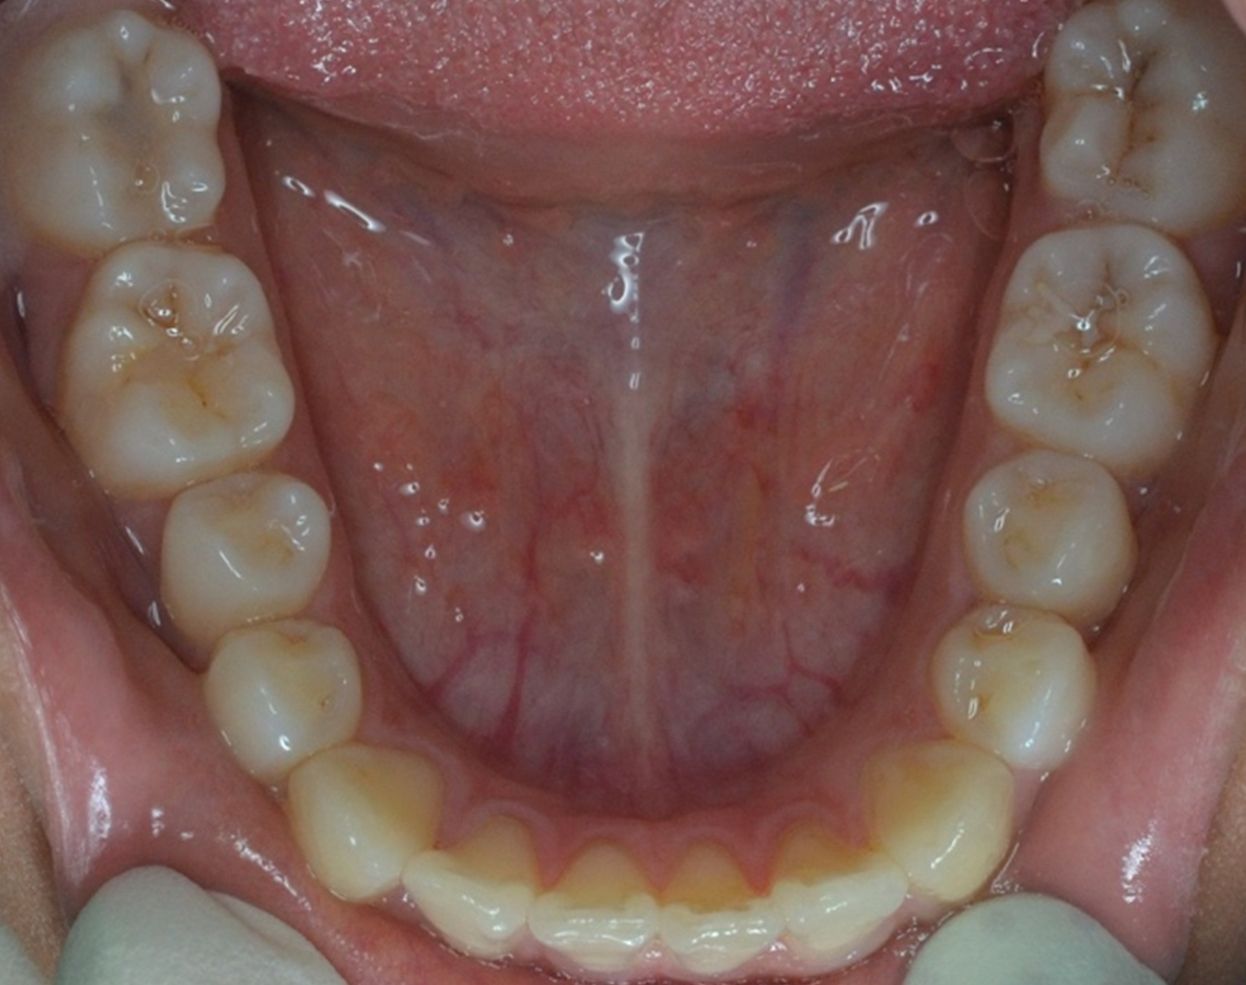

A continuación, mostramos el caso de una paciente adulta con clase II ósea y dentaria.

Con Ortodoncia Invisible, y gracias a la cooperación de la paciente, conseguimos este resultado y, lo más importante de todo, que la paciente sonría sin complejos.